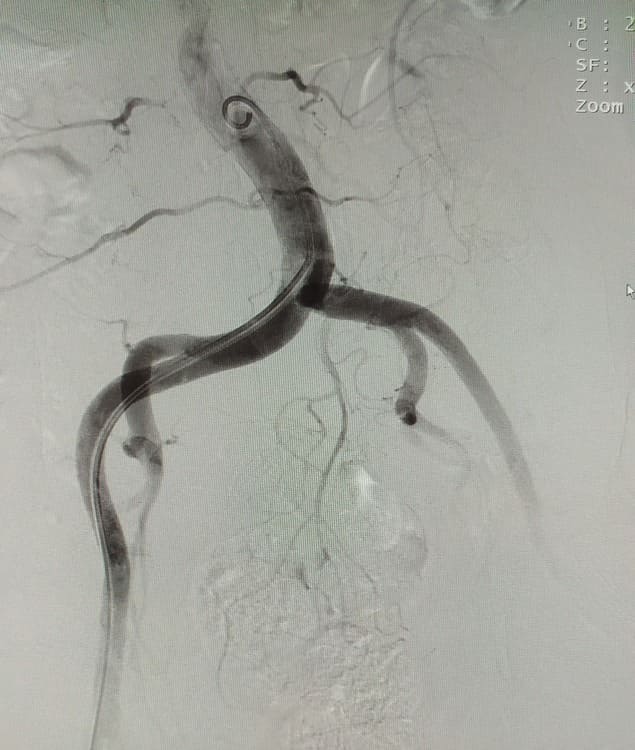

Зазвичай люди літнього віку мають вражені атеросклерозом та звивисті, внаслідок гіпертонічної хвороби судини. Цей випадок не був виключенням, тому нам довелося докласти максимум зусиль, використати високотехнологічне обладнання та інструменти, щоб віднайти цільові судини. На диво, незважаючи на попередню операцію, судинний малюнок рецидивної простати збігався з тим який буває у не оперованих пацієнтів. Тому нам вдалося їх чітко визначити з обох сторін та заповнити емболами. Це доволі кропітка праця, адже щоб викликати ішемію, необхідно поступово виключити кровоплин в усій тканині залози. Полегшувало операцію лише відсутність перетоків артерій на сусідні органи. Це дозволило нам безпечно емболізувати, не боячись негативних наслідків та ускладненнь.

Операція була виконана 28.05.2021. під місцевою анестезією, доступом через прокол в правій стегновій артерії. Вже на протязі тижня зменшилась кількість походів в туалет по маленькому (вночі до 1 разу), полегшилось сечовиділення та покращилось самопочуття хворого.